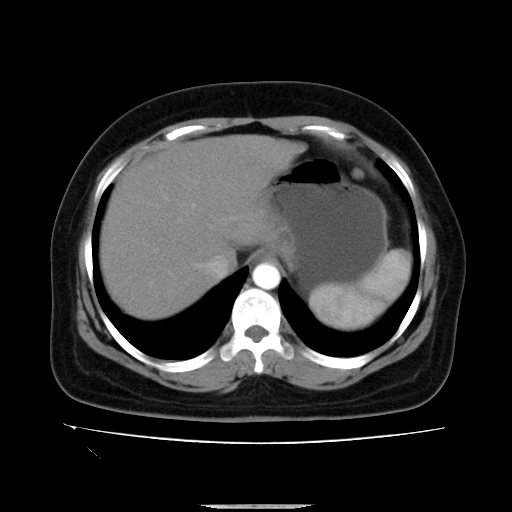

标题: CT14225:女性46岁。当地B超示肝内占位,来我院作CT检查。请 [打印本页]

标题: CT14225:女性46岁。当地B超示肝内占位,来我院作CT检查。请

肝内结节强化特点符合原发性肝癌表现,脾脏改变考虑为增大及先天发育所致。

动脉期病原灶明显强化高于肝密度且中央有无强化区,静脉期强化程度下降明显,延迟低于肝密度,考虑肝腺瘤可能性大,

符合肝癌表现,脾脏大(肝硬化?)

肝内结节强化特点:快进快出符合原发性肝癌表现

非常典型,肝ca,脾脏先天性发育异常,脾大

此患者虽然符合快进的特点,却不符合快出的特点,因为门脉期几乎是等密度,不符合肝癌的增强表现,所以我考虑肝局灶性结节增生可能性大

肝内结节强化特点符合原发性肝癌表现。脾大。

快进快出,符合肝癌表现。脾脏改变考虑为增大及先天发育所致。